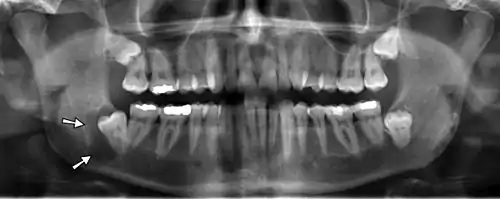

Panoramic radiographs have the capability to demonstrate a portion of the neck and display atheromas (calcifications in the carotid artery) which are an indication of both local and generalized (systemic) atherosclerosis. Atherosclerosis of the coronary arteries leading to myocardial infarction (heart attack), and atherosclerosis of the carotid artery leading to stroke are the number one and number three most common causes of death in the United States.[6]

There is interest to look at panoramic radiographs as a screening tool, however further data is needed with regards if it is able to make a meaningful difference in outcomes.[7]

Epidemiology: general public and high risk groups

Additional research projects have further determined the prevalence rate of these atheromas in the general population (3–5%)[8][9] and among high-risk groups (over 25% in: recent stroke victims,[10] individuals with obstructive sleep apnea syndrome,[11][12][13] postmenopausal women,[14] type 2 diabetics,[15][13][16] individuals with dilated cardiomyopathy,[17][13] and among individuals who have received radiotherapy directed at the neck,[18][19]). These findings have been corroborated by other several other researchers.[20][21][22][23][13]